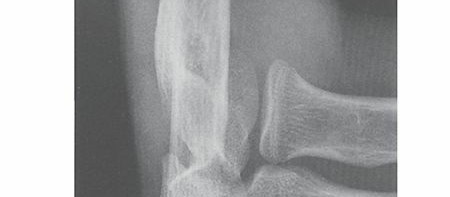

- Radial Shaft Fractures & DRUJ Instability: Epidemiology, Anatomy, and Management of Galeazzi Lesions

Radial Head Fractures: Symptoms, Diagnosis & Recovery